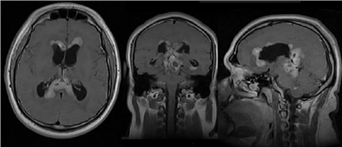

Imagen 3 Imágenes heterogéneas con lesiones con reforzamiento al contraste, también se observa dilatación de ventrículos laterales y 3er ventrículo.